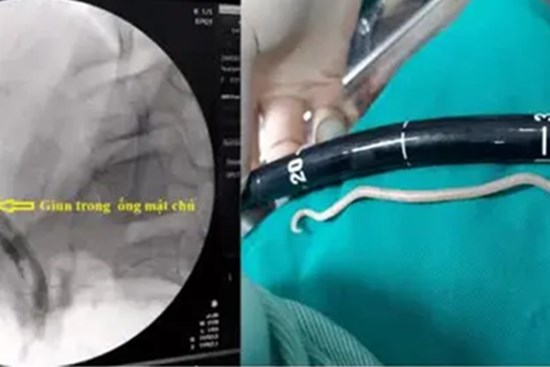

Nội soi gắp giun đũa dài gần 20cm trong ống mật chủ bé gái 11 tuổi

Bệnh viện Bãi Cháy (Quảng Ninh) vừa tiến hành nội soi mật tụy ngược dòng gắp giun đũa dài gần 20cm trong ống mật chủ của bệnh nhi 11 tuổi.